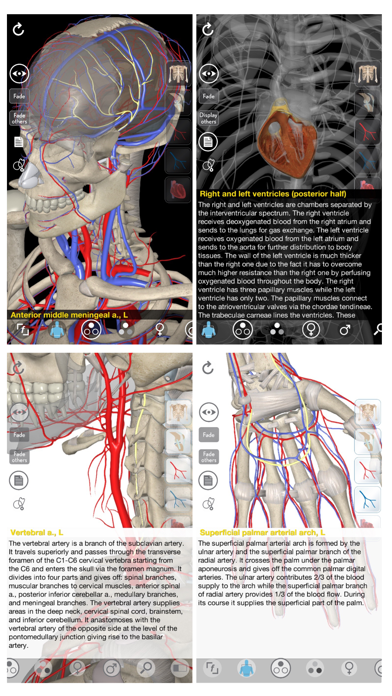

1. 3D Organon Anatomy – Heart, Arteries, and Veins is a feature-rich interactive cardiovascular atlas enhanced with quality anatomy descriptions and texts with frequently encountered clinical correlations.

2. + Included structures: Heart (myocardium, ventricles, atria), Heart valves, Pericardium, Great vessels, Arteries of the body (all regions), Veins of the body (all regions).

3. The 3D anatomy models can add important cognitive input for understanding the spatial relationship between anatomical structures and landmarks leading to an increased retention of knowledge.

5. Learn heart and vascular anatomy with thousands of realistic anatomical models/structures.

11. + Visualize anatomy using the latest 3D technologies.